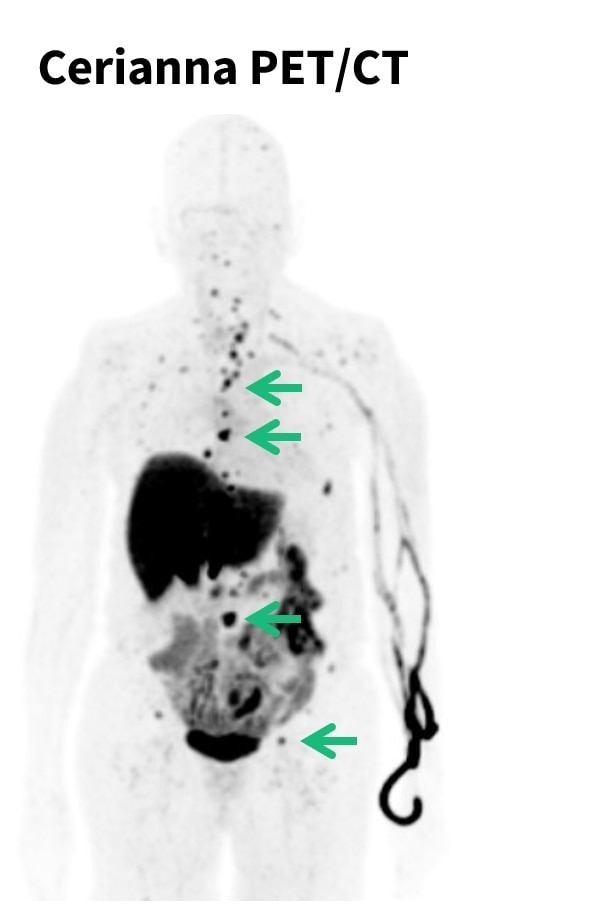

Omni 128cm total body PET/CT system

GEHC announced CE Mark for its next-generation Omni 128cm total body positron emission tomography / computed tomography (PET/CT) system.